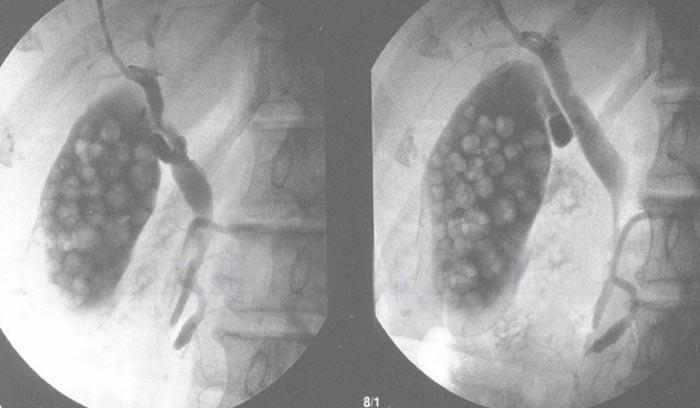

Желчнокаменная болезнь

Распространенное заболевание, при котором образуются застои желчи, ее состав меняется, происходит образование конкрементов — желчных камней. Камни могут состоять из холестерина, билирубина, иметь смешанный состав. Образование камней опасно закупоркой протоков, появлением колик, развитием тяжелых осложнений (рис. 3).

Желчнокаменная болезнь чаще развивается у женщин. Ее вызывает нарушение обмена холестерина и билирубина, воспаление желчевыводящих путей, ухудшение оттока желчи. Это происходит под влиянием разных факторов, включая пожилой возраст, наследственную предрасположенность, неправильное питание, малоподвижный образ жизни, голодание, соблюдение строгих диет, гормональные нарушения или состояния, при которых повышается уровень эстрогена.